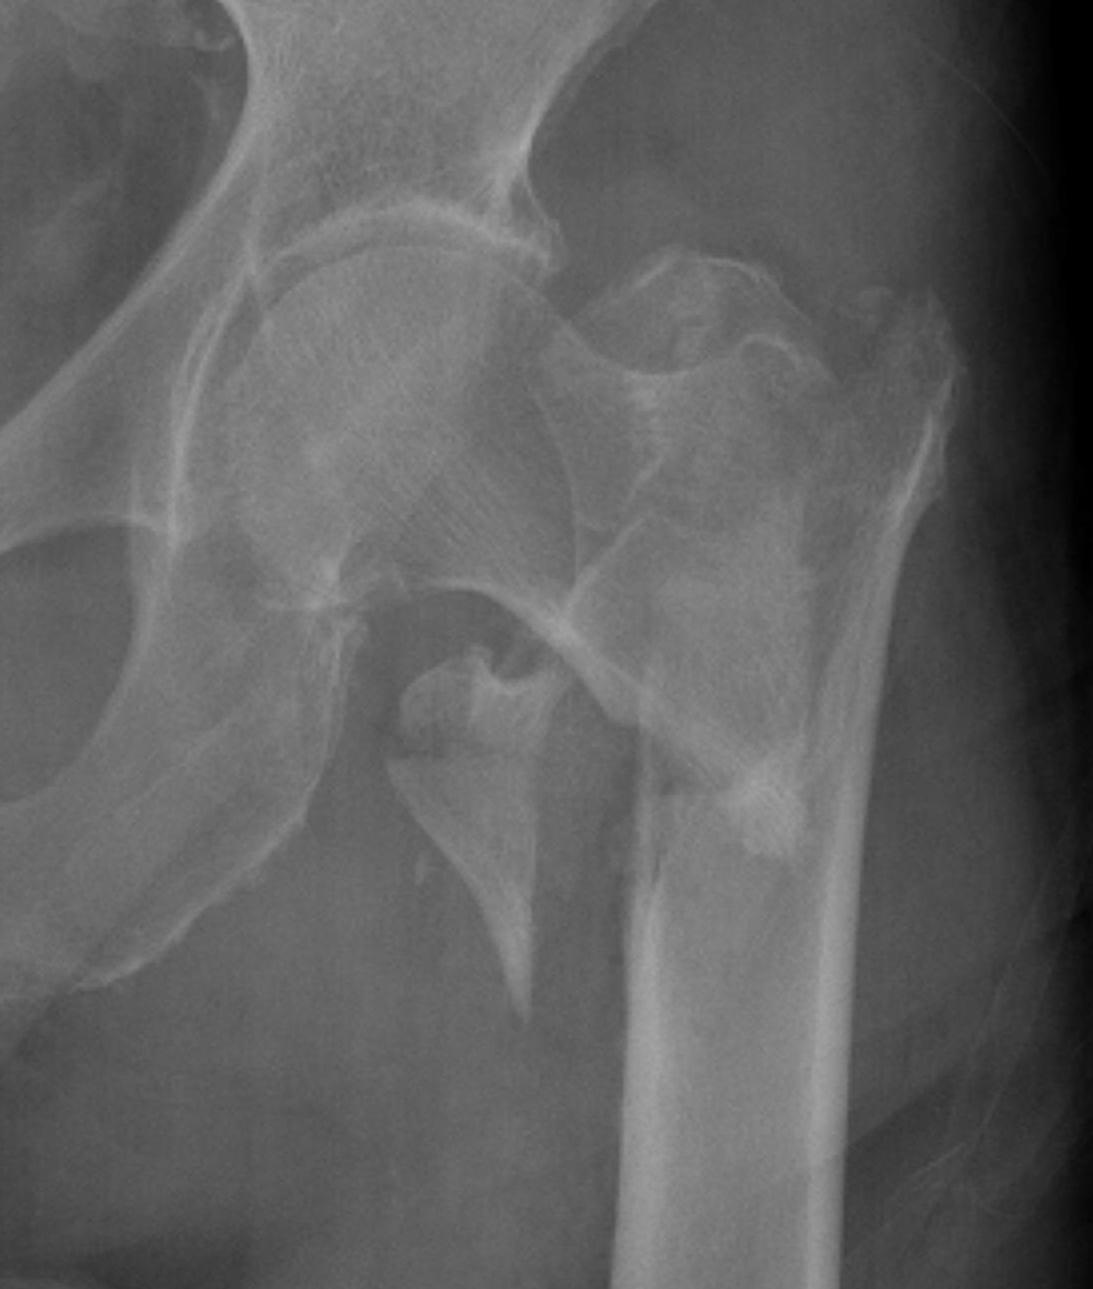

Definition

Fracture which extends between the trochanters of the proximal femur

Extra capsular / well vascularized

Evans Classification

Two main types

- Type 1 Intertrochanteric

- Type 2 Reverse Oblique

Type 1 Intertrochanteric

2 part undisplaced

2 part displaced

3 part without posterolateral support (GT fracture)

3 part without posteromedial support (LT fracture)

4 part without posterolateral or posteromedial support

Type II Reverse Oblique Type

Inherently unstable - tendency of femoral shaft fragment to shift medially

Reverse oblique fractures